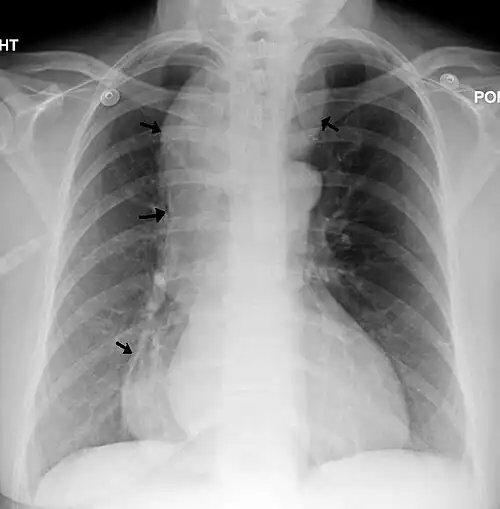

Aspecto radiográfico

Un esofagograma con rayos X (fluoroscopia), puede mostrar la disminución de los movimientos peristalticos, la dilatación del esófago medio y superior (proximal) y el estrechamiento del esófago en su parte inferior (distal), con estrechamiento en el esfínter esofágico inferior y reducción del diámetro en la unión gastro-esofágica. La imagen que proyecta se denomina clásicamente «en pico de loro» o «en cola de ratón». Por encima de la reducción, el esófago a menudo se observa con una dilatación de diversos grados a medida que poco a poco se va estirando en el tiempo. Por la falta de movimientos peristálticos, se suele observar en la radiografía un margen entre aire y líquido.